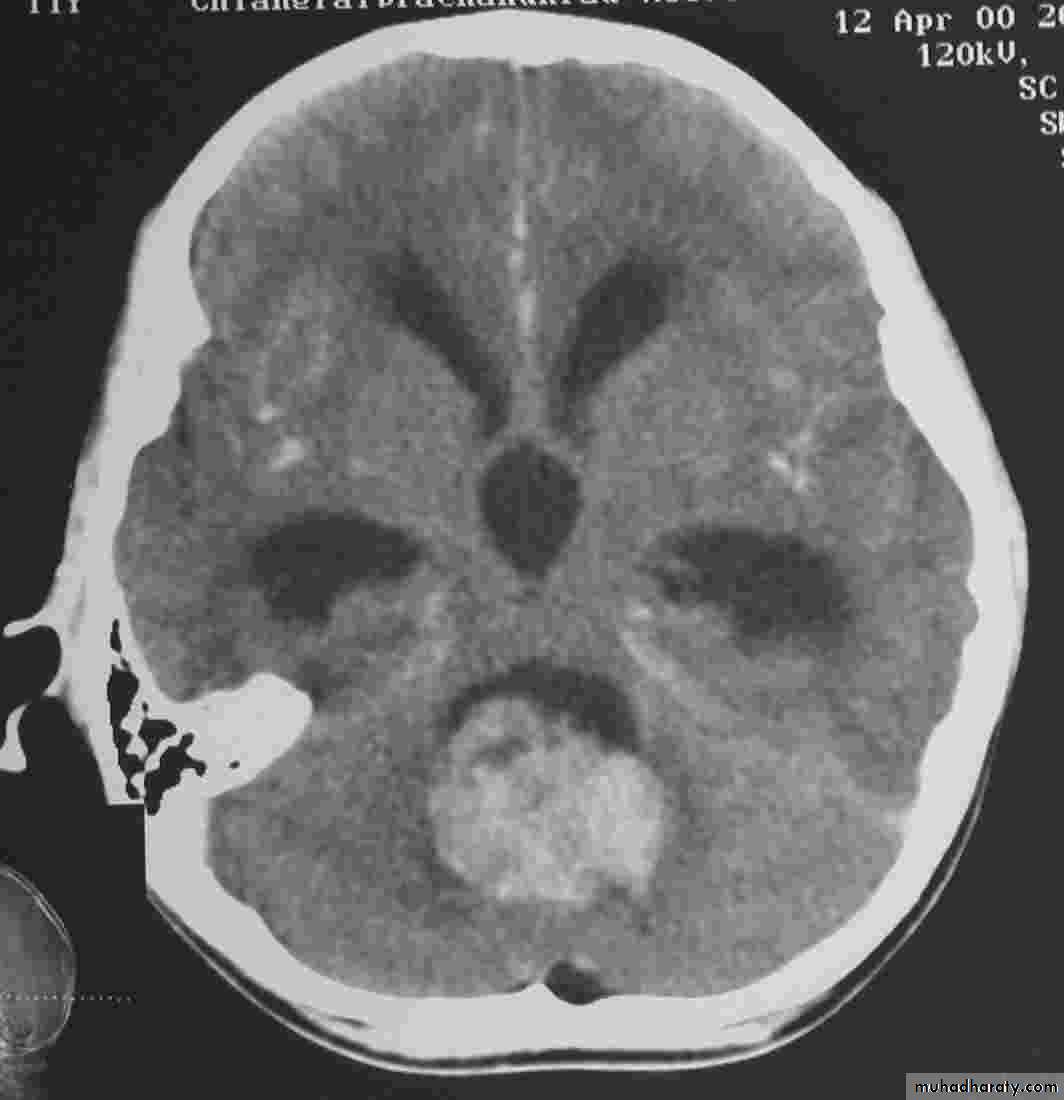

Secondary metastasis

Old age group above 50 Y , any lesion within the cerebellar hemisphere it is secondary metastasis unless proven otherwise F. from breast CA M. from bronchogenic CA .

Appear as nodular single or multiple lesion hypo dense or hyper dense .

Surrounded by per focal edema

Enhanced as solid or ring pattern of enhancement .